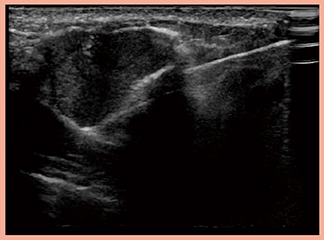

4G CMUTでは,乳がんの術前化学療法後のマーキングクリップや,乳房の一次再建術後に注入したエキスパンダーの後方も良好に視認できる。超音波ガイド下手術での線維腺腫の摘出術に用いる外科剪刀も,4G CMUTでは反射が非常に少なく描出でき,さらに,高い透過性により病変を明瞭に確認できるため(症例4:図4),切除マージンをほぼゼロに切除できる点も魅力的である。

図4 症例4:線維腺腫の超音波ガイド化手術